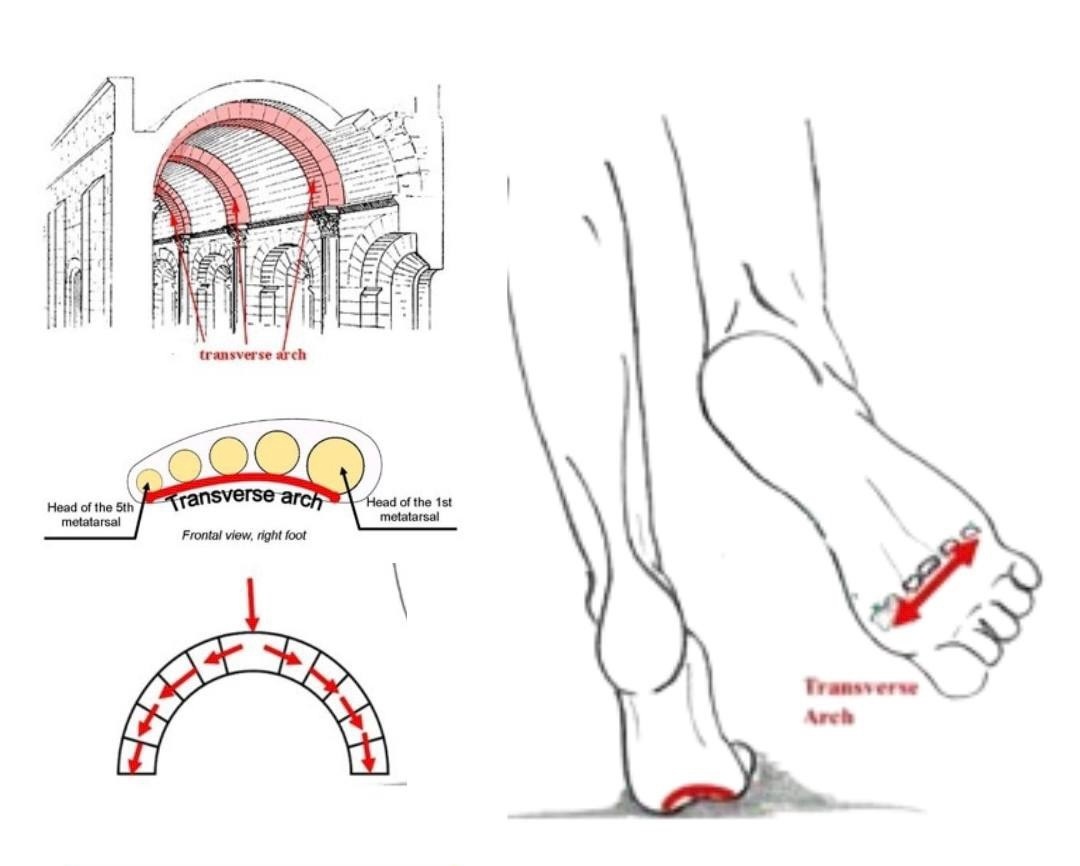

足弓塌陷 今天继续讲讲横弓的问题——横弓塌陷最常见的表现,首先是“踇外翻”,也就是常说的“大脚骨”,是指踇趾在第一跖趾关节处向外侧过度偏斜移位,即大踇趾过度向脚外侧偏移。

【为什么横弓会塌陷】1. 先天性扁平足,或者韧带肌肉较为松弛无法支撑足弓。2. 鞋跟过高,鞋头过尖第一跖趾关节压力太大导致拇外翻。3. 体重过大压迫足弓使其塌陷。